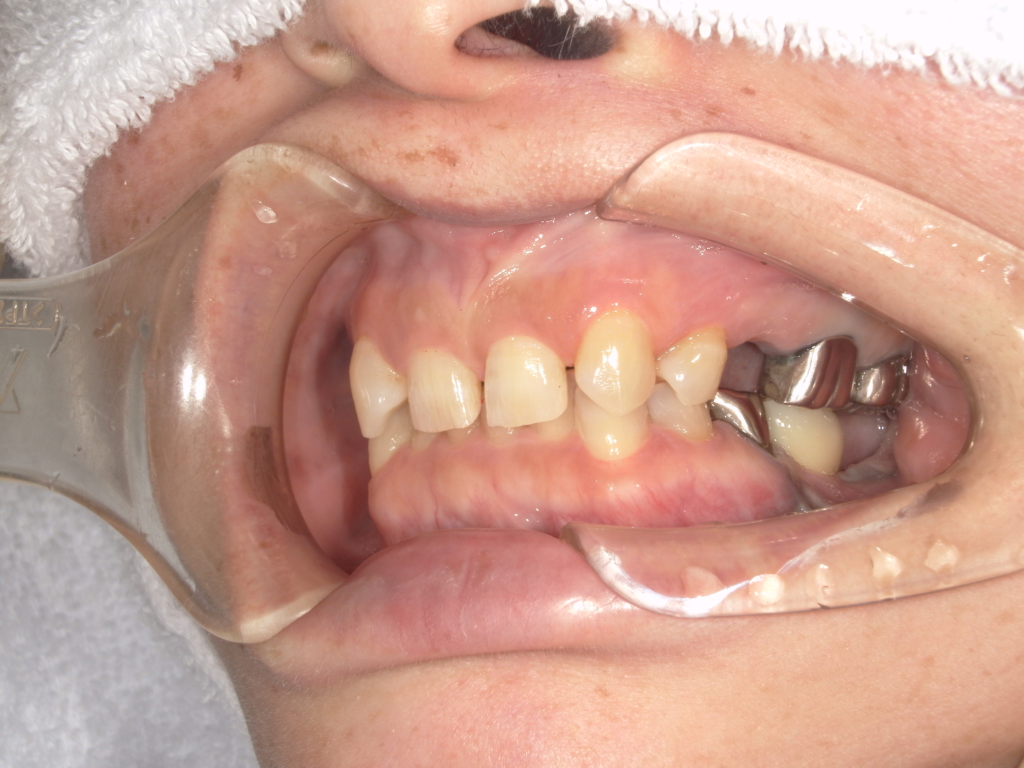

N様 50代 男性 インプラント実例 #37

前歯の4本が、残すのが難しい状況となり、インプラント治療を行いました。

インプラントは前歯に2本埋入し、4本の前歯を作っています。歯を抜くと同時にインプラントを埋入し、仮歯を作りました。その後2ヶ月で、被せ物を入れました。被せ物は、セラミックスで作っています。

治療前

治療後